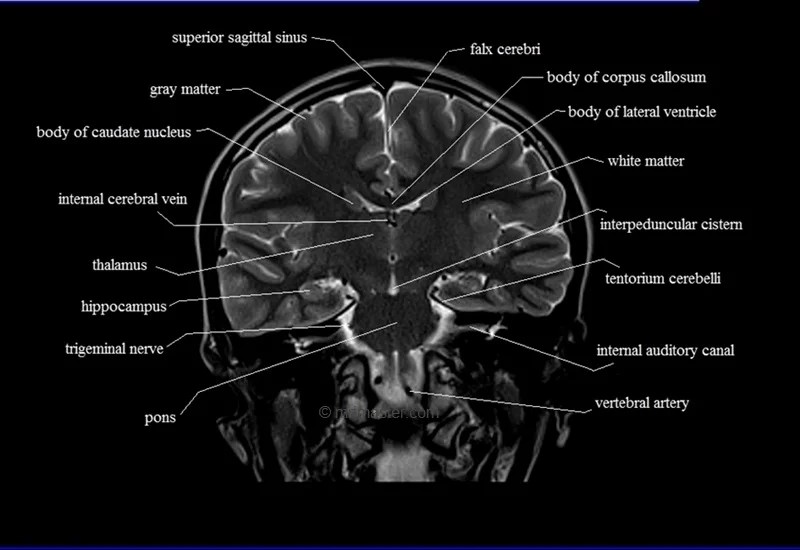

MRI Coronal Cross Sectional Anatomy of Brain

This MRI brain cross-sectional anatomy tool is absolutely free to use. Use the mouse scroll wheel to move the images up and down, or alternatively, use the tiny arrows (→) on both sides of the image to navigate through the images.